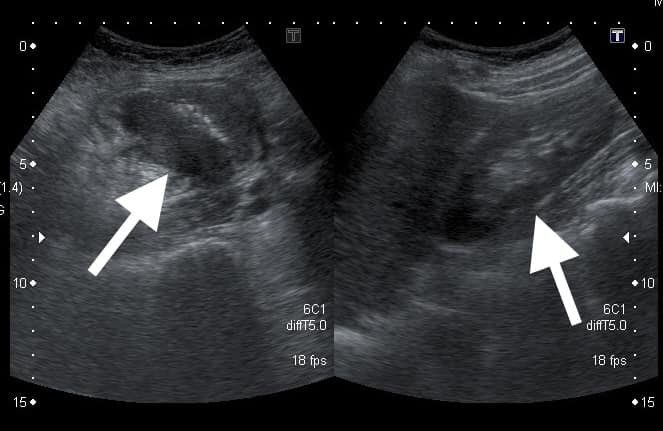

圖/翻攝自 臉書/錢政弘 胃腸肝膽科醫師 ▲ 錢政弘曬出超音波照片,右圖箭頭處是患者的右側腎臟,左圖箭頭則是「偽腎臟」。

錢政弘表示,隔天進行腹部超音波檢查時,發現女患者的右下腹有一個不尋常的構造,疑似多了一個大約5公分的腎臟,且位置正是患者壓痛的地方,讓他頓時感覺不妙,直言「這是偽腎臟(pseudokidney sign),通常不是發生腸套疊就是大腸癌」,隨後錢政弘替女患者做大腸鏡檢查,驚見盲腸裡有一個環形生長的腫瘤,切片後證實是大腸癌。